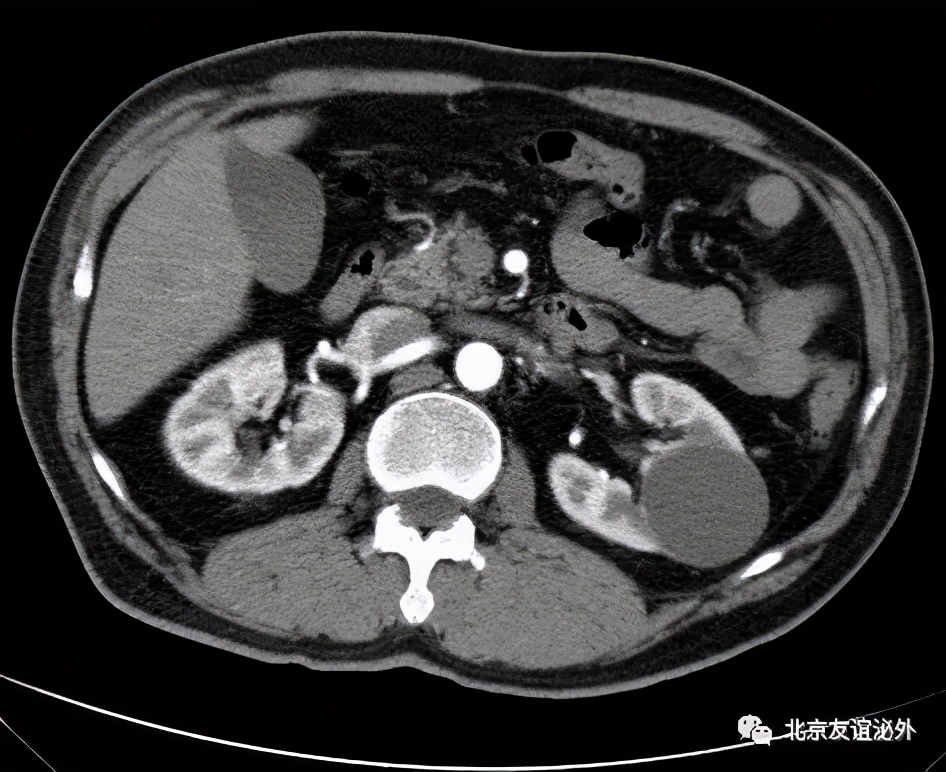

图3. Bosniak II级良性囊肿(囊肿内少量细小分隔)